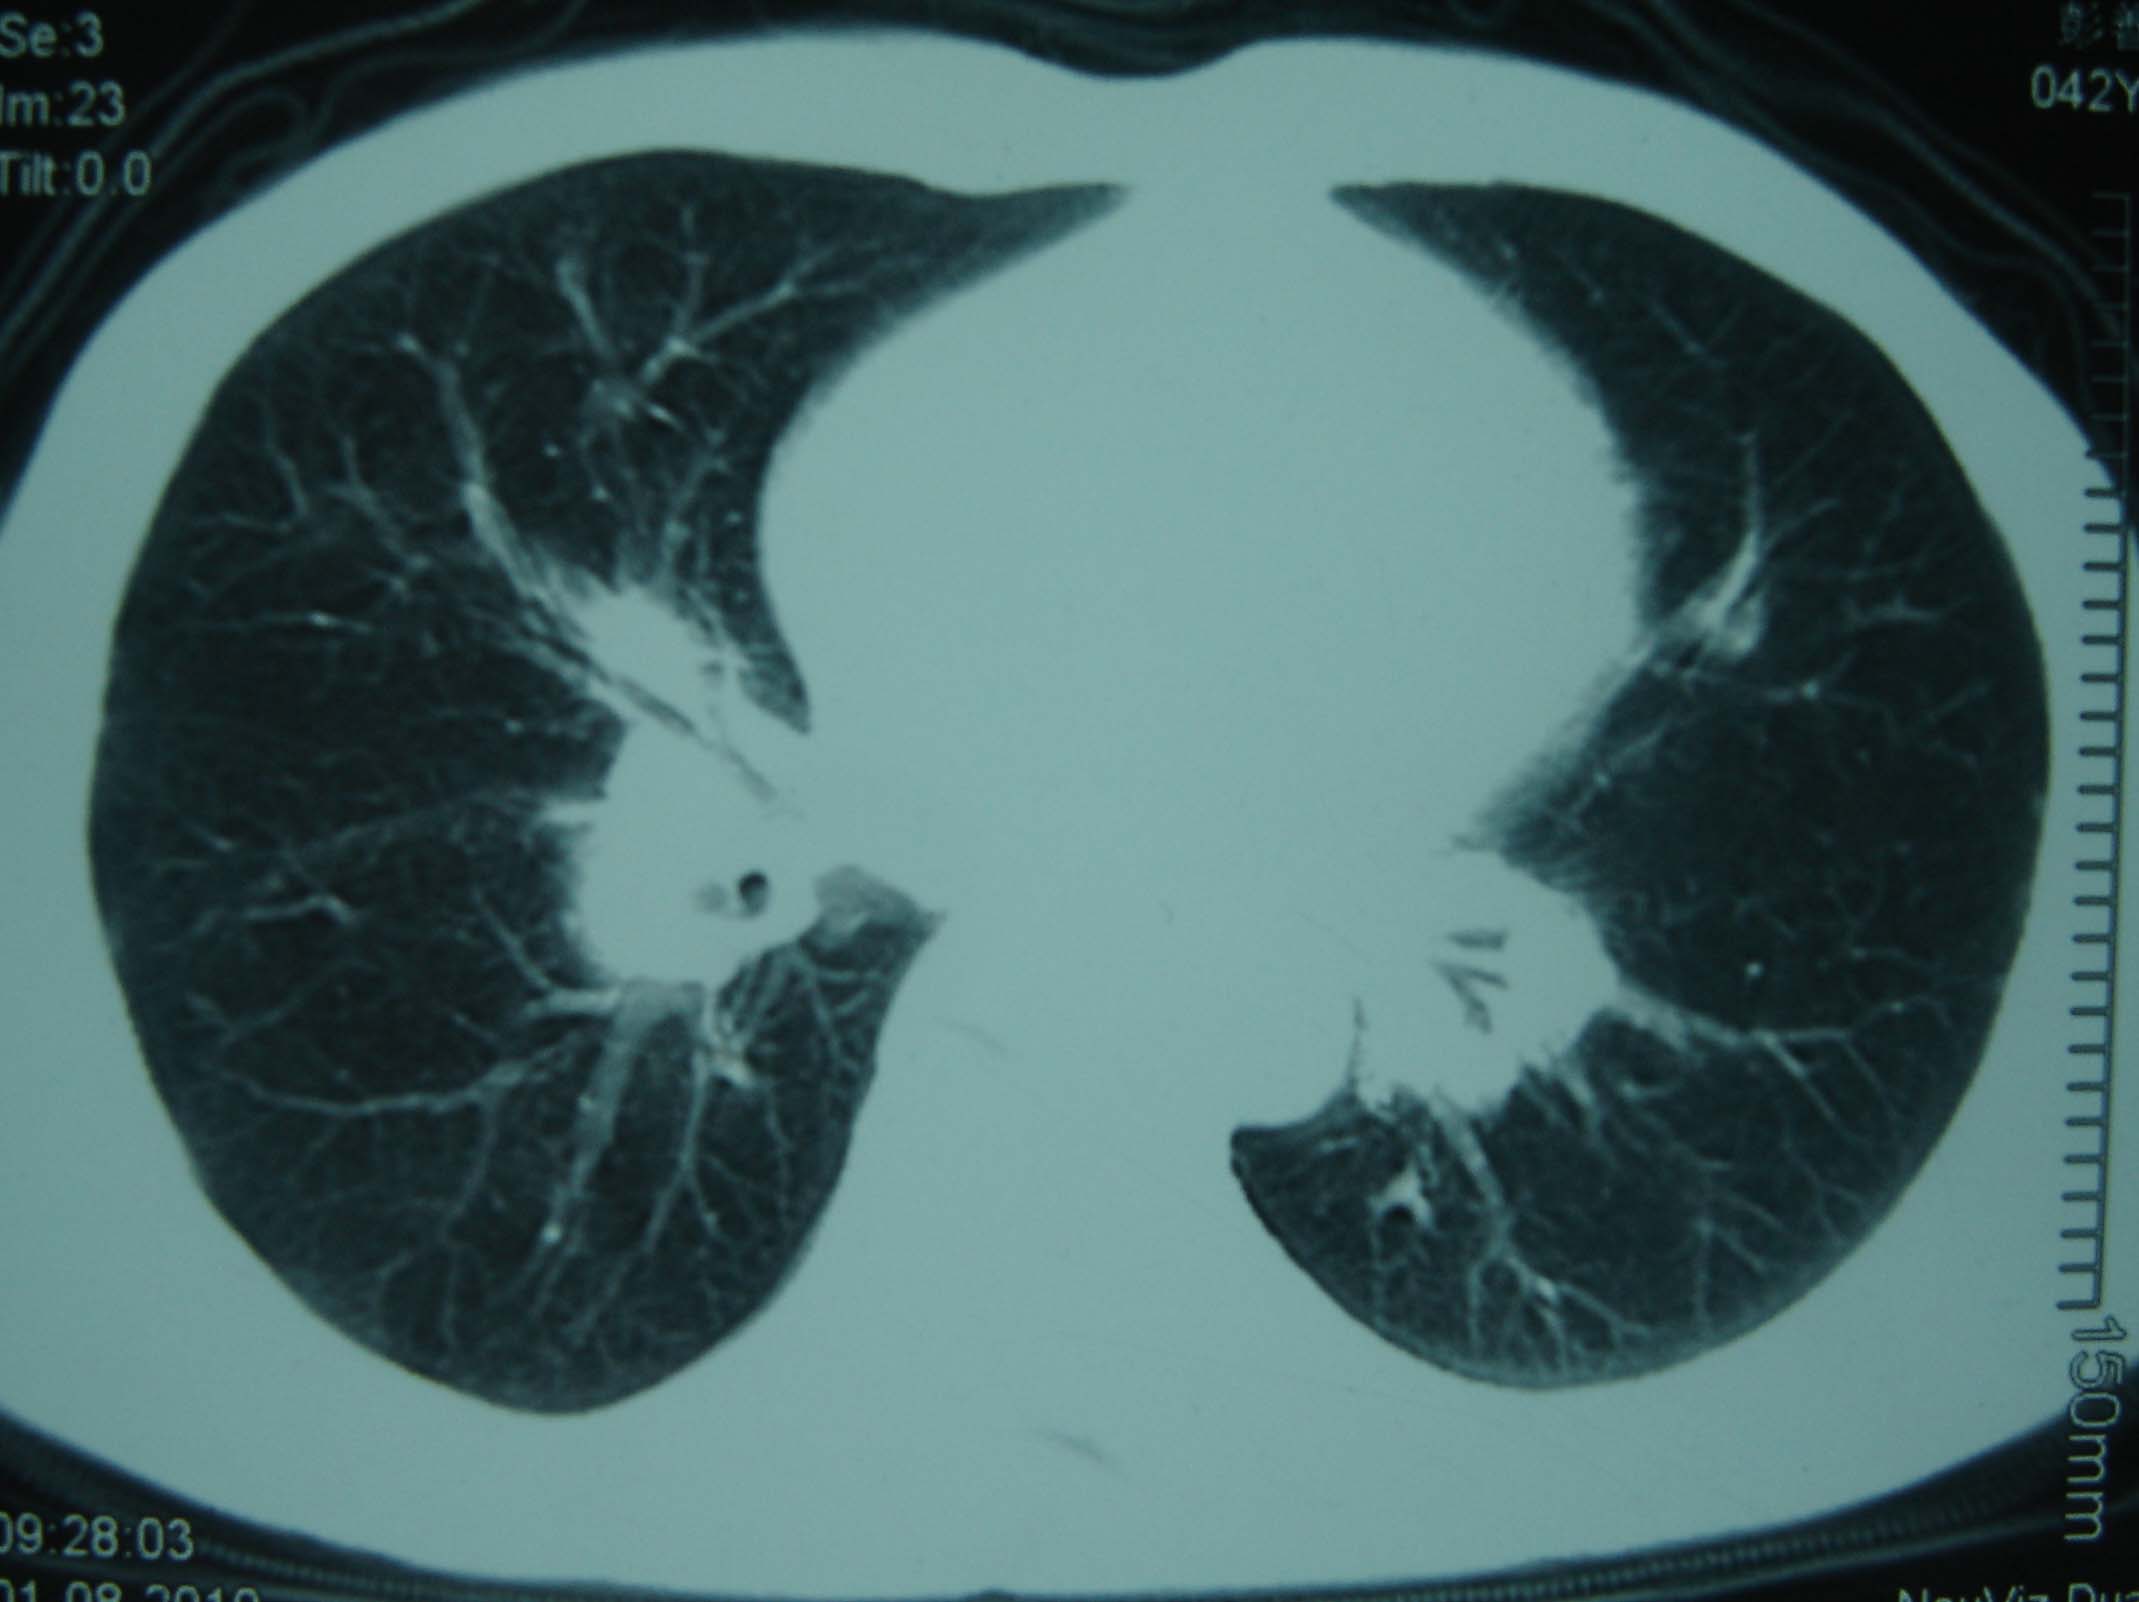

标题: CT25321:两肺多发结节 请会诊 [打印本页]

标题: CT25321:两肺多发结节 请会诊

男 、43岁,咳嗽胸痛,装修工,平时接触粉尘较多,有吸烟史10多年,纤维支气管镜检查未发现异常,胃镜、腹部b超检查亦未发现异常,颈部淋巴结活检未发现肿瘤细胞。

不能排除转移,如果不能找到原发灶,只有短期随访。

结节病?转移瘤?

结节病。

转移瘤?

1)考虑双肺及胸膜多发性转移瘤。2)肺气肿。

双肺结节病。